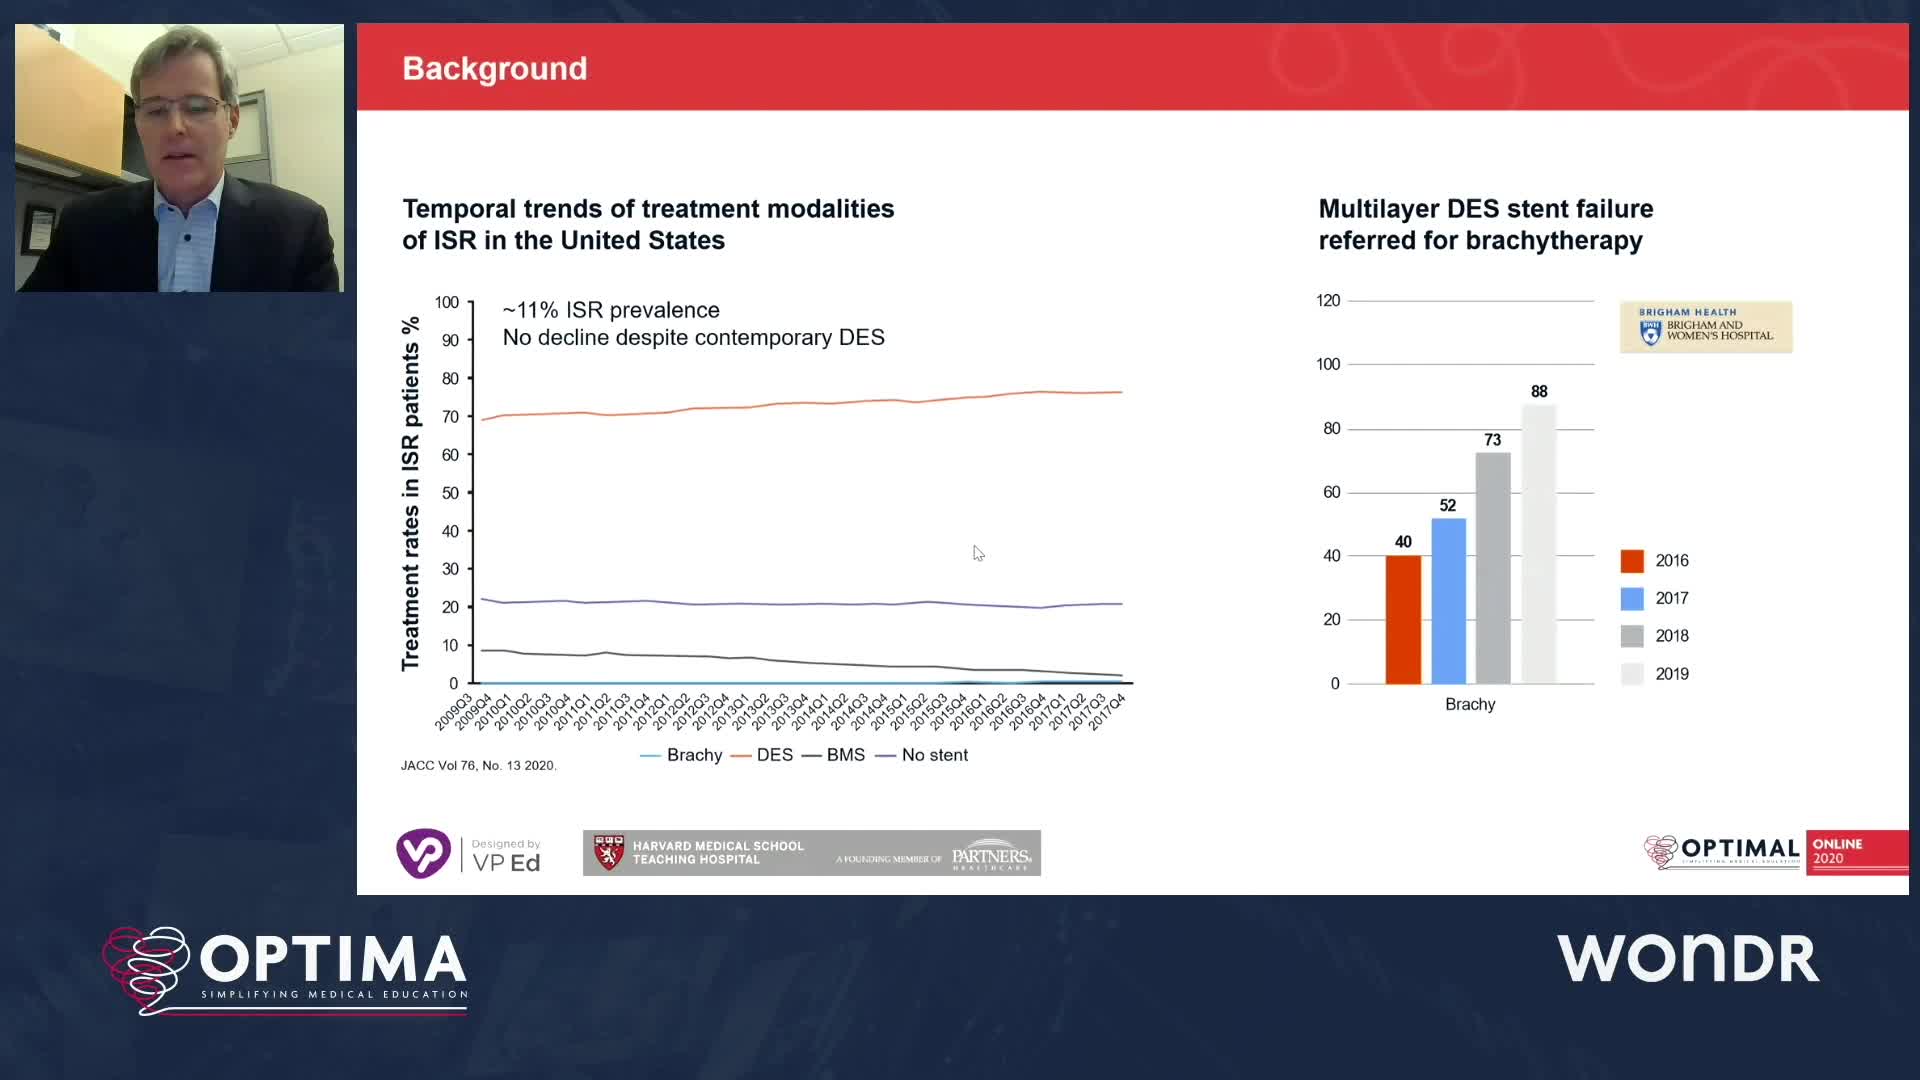

Session 3: Stent failure – can we ignore this?

Optimal Online 2020

Optimal Online 2020 - Day Three